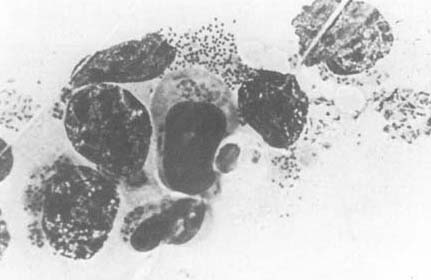

| Comment: | Theileria parva, an intracellular parasite, causes the East Coast Fever. This disease affects wild and domesticated ruminants and represents a major economic problem in many parts of Eastern, Southern, and Central Africa. |